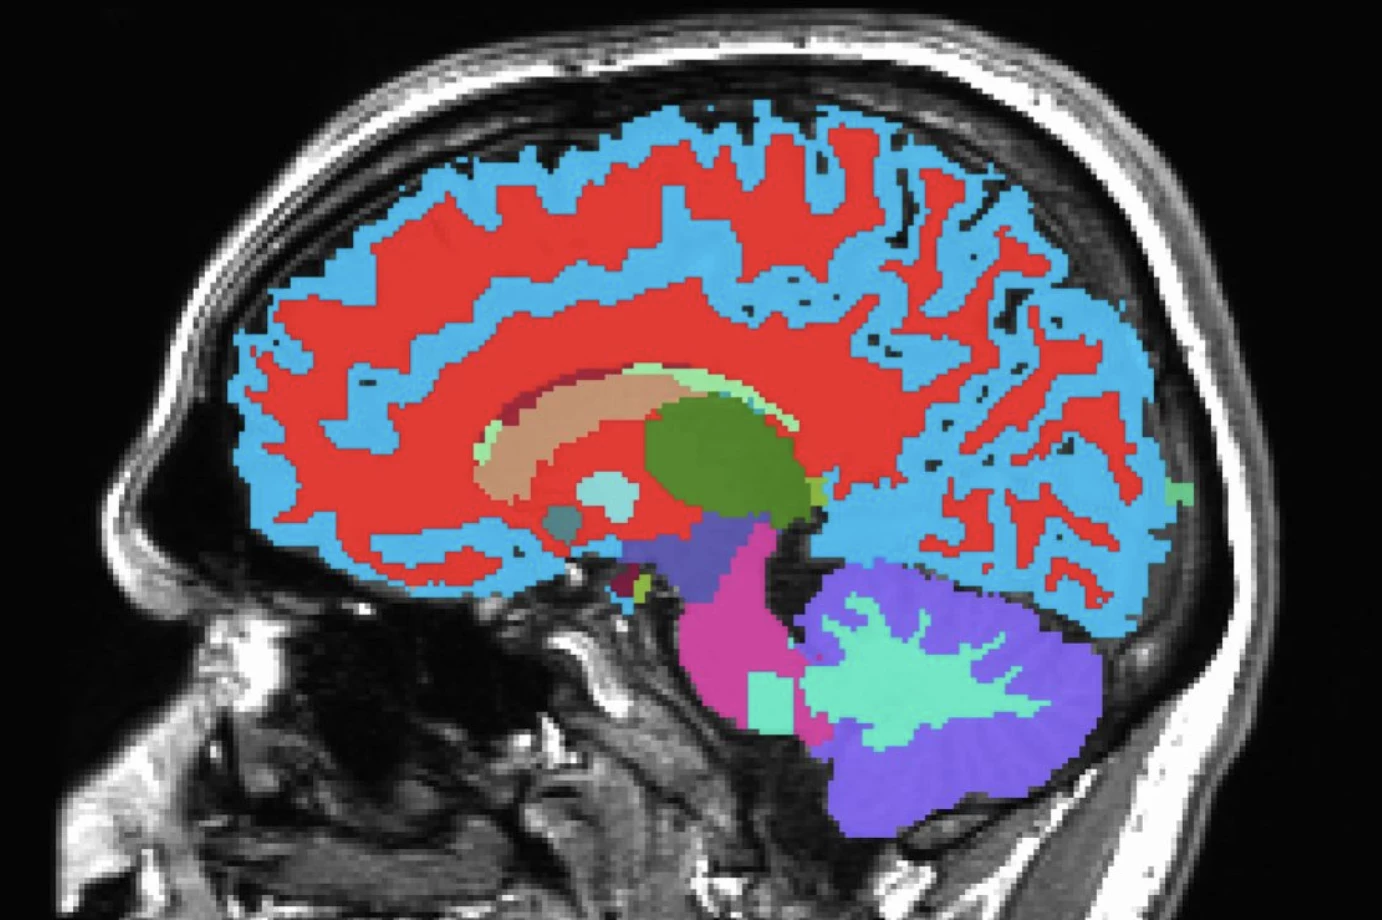

A single, freely available, noninvasive brain scan done in just a few minutes during midlife can predict what chronic diseases are most likely to appear in the future, empowering people to make diet and lifestyle changes that mitigate their risk even decades before symptoms begin to show. Getting the jump on degenerative conditions like Alzheimer's disease could have a huge impact on health outcomes later in life.

Scientists at Duke and Harvard Universities and the University of Otago have developed the Dunedin Pace of Aging Calculated from NeuroImaging (DunedinPACNI) scan, which as the name suggests, scans the brain to determine how fast it is aging. It didn't just predict cognitive impairment, accelerated brain atrophy and conversion to diagnosed dementia, it could also provide a risk factor for physical frailty, poor health, other future chronic diseases and mortality.

Training the tool on 860 New Zealanders born between 1972 and 1973, who have been studied since birth, DunedinPACNI is based on scans of their brains taken at age 45. Through this foundation, covering around 20 years of brain health and other metrics such as blood pressure and organ function, the system can estimate a score for how quickly each person is aging.

While the concept is not a new one – AI has rapidly accelerated the development of predictive diagnostics – the DunedinPACNI tool differs in that its base learning is on the same individuals as they grew older, not a population of different people who had received scans. Because seeing how one person's brain looks at, for example, age 35, and another person's brain at age 60, those methods become more age-based across a population than a longitudinal measure of each individual.

A constant seen across all datasets was that a faster aging score when it came to brain function was closely tied to poorer performances on cognitive tests and greater shrinkage in the memory region of the hippocampus. These people were also much more likely to have pronounced cognitive decline in the future.

When the team used their tool to assess Alzheimer's disease risk, using 624 brain scans from individuals aged 52 to 89, the people who were highlighted as the fastest aging when they started the study were 60% more likely to develop dementia.

DunedinPACNI results weren't just confined to brain health, with faster aging increasing the likelihood of higher frailty and age-related conditions like heart attack, lung disease and stroke. In fact, those who were aging fastest in midlife were 18% more likely to develop a chronic disease within just years, compared to individuals who had average aging scores. These fast agers were also 40% more likely to die within this window of time.

The researchers also plan to look at other factors – mental health conditions, poor sleep – through the DunedinPACNI lens, to see how individuals may age differently. While more work is needed to turn the tool into an everyday clinical assessment, it's expected to first be used by medical researchers assessing aging via MRI data, to uncover specific aging biomarkers that can't be identified through other tests like blood samples.